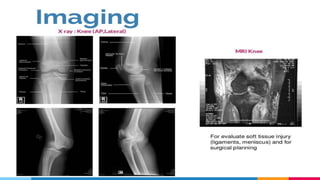

Knee dislocation

brief introduction about knee dislocation.